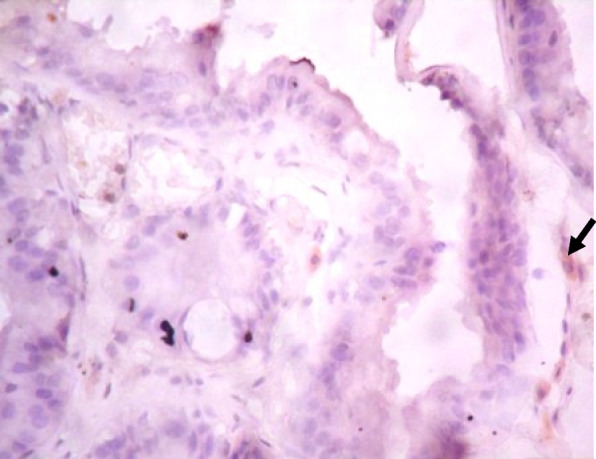

Immunohistochemistry of COX-2 and iNOS in prostate gland

IHC staining of prostate tissue revealed weak expression of COX-2 in the control (Fig. 7), LSD (Fig. 8), SSD (Fig. 9), and moderate expression in HSD group (Fig. 10). Meanwhile, there was weak expression of iNOS in prostatic tissues of rats in the control (Fig. 11), LSD (Fig. 12), SSD (Fig. 13) and HSD (Fig. 14).

Fig. 10.

Section shows moderate expression of COX-2 in the prostate epithelium (black arrow) x 400